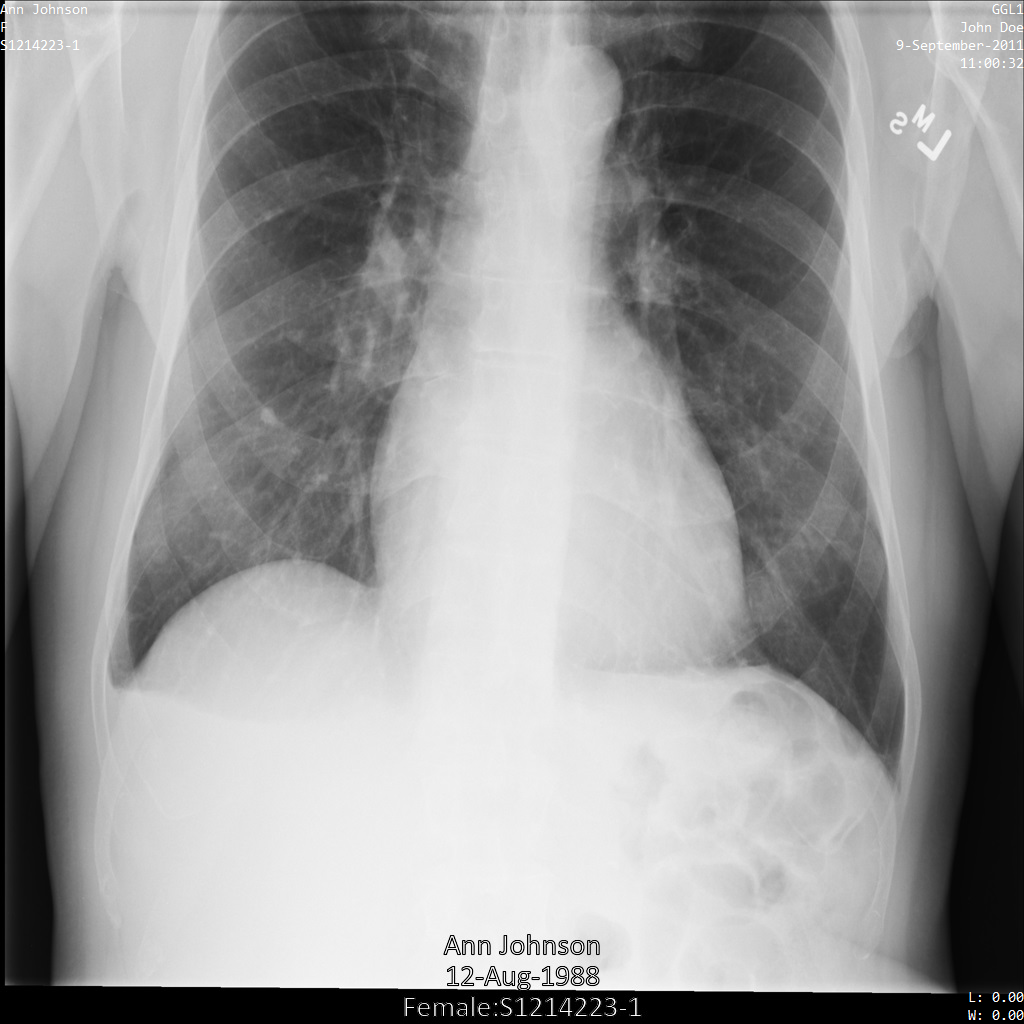

En los siguientes ejemplos se muestra cómo desidentificar un conjunto de datos que contiene almacenes DICOM y datos DICOM mediante el perfil de filtro de etiquetas ATTRIBUTE_CONFIDENTIALITY_BASIC_PROFILE.

Este perfil de filtro de etiquetas elimina las etiquetas basadas en el perfil básico de confidencialidad en los atributos del estándar DICOM.

Después de enviar la imagen a la API Cloud Healthcare mediante el perfil de filtro de etiquetas ATTRIBUTE_CONFIDENTIALITY_BASIC_PROFILE, la imagen aparece de la siguiente manera. Aunque los metadatos que se muestran en las esquinas superiores de la imagen se han ocultado, la información personal protegida que aparece en la parte inferior de la imagen sigue ahí.

Para eliminar también el texto insertado, consulta el artículo Ocultar el texto insertado de las imágenes.